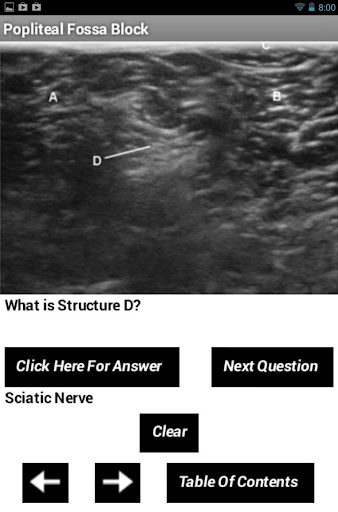

Unlike websites or videos, this app is interactive since there is a screen where you can draw right on the pictures. For instance in the fourth screen shot, the path button was clicked and a gray arrow appears showing a possible needle path. Next the draw button was clicked and I was able to circle the sciatic nerve right on the screen. You can draw an x to mark an artery, circle nerves or initial the names of muscles right on the screen. The last screen for each block is a quiz so you can test your knowledge of the relevant structures. It’s a great way to review the anatomy and teach others.

For each block, there are a series of ultrasound pictures with the anatomic structures labeled. On the next screen, there is a Draw button. Once clicked, the Draw button turns gray and you are able to touch the screen and draw on the image. It’s possible to draw what your needle path would look like or you can mark the important structures. There is also a Path button which show where a needle path might lie when doing the block. The Clear button will clear the screen. If the Path button is clicked first and the draw button second, you can mark the anatomic structures around the needle path. The last screen for each block is a quiz of the structures. This app is not a comprehensive how to guide for everything there is to know about every ultrasound guided block, but it is a nice interactive way to increase your knowledge. It is not possible to touch zoom in and out on the pictures, but the pictures will expand in landscape mode.

Popliteal Fossa